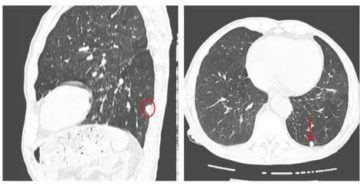

Очаги в лёгких на КТ — что это может быть и как выглядят очаговые изменения…